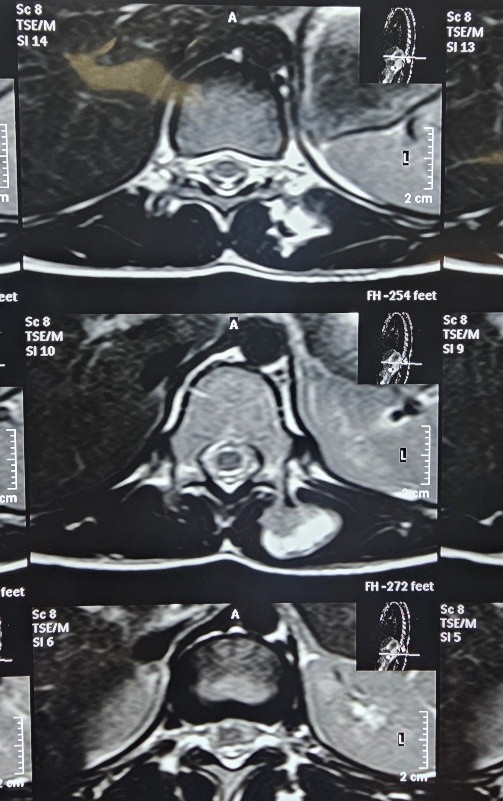

An 11-year-old female presented with the complaints of gradually progressive swelling in the mid-back region with discomfort on lying down in the supine position. On physical examination, we found a globular, non-tender bony hard swelling of size 5 cm × 3 cm on the left para-spinal region of D11-D12 vertebra. The surface was smooth, and margins were well defined. The lesion was found to be arising from D12 Vertebrae with normal overlying skin. There was no neurological symptom and no similar swelling elsewhere in the body. The plain X-ray anteroposterior and lateral views of the dorsolumbar spine were unremarkable. The non-contrast magnetic resonance imaging (MRI) of the dorso-lumber region showed a well-defined extra-medullary lesion arising from the left mammillary process of D12 vertebra with a cartilage cap of 2 mm thickness. The medullary cavity of the lesion was found to be in continuity with the parent bone (Fig. 1).

Figure 1:Axial MRI Showing Bony outgrowth